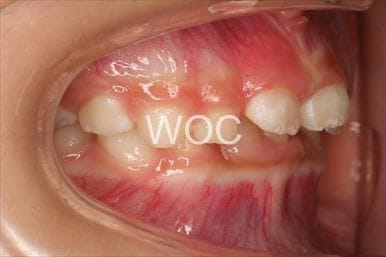

開咬

治療前1

治療前2

- 年齢:5歳4ヶ月

- 主訴:前歯で噛めない、おしゃぶりがやめられない

- 診断名:開咬

- 装置:機能的矯正装置

- 期間:5年2ヶ月 ※

- 費用:基本矯正料金:370,000円